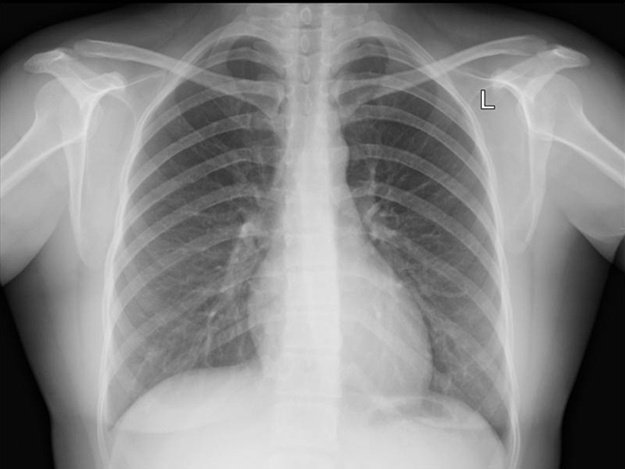

- рентгенологическое исследование;

- флюорография;